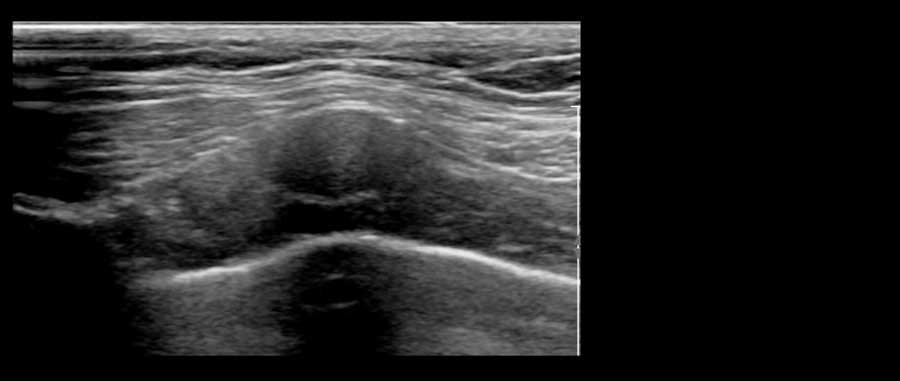

Một xương sườn nhô ra có thể tạo thành một khối cứng lồi lên, dễ nhầm lẫn với khối u vú.

Bệnh nhân này than phiền về một khối cứng đau trong vú.

Trên siêu âm, ghi nhận hình ảnh khớp sụn-xương sườn nhô ra.

Đây là vị trí tiếp nối giữa phần xương đã vôi hóa của xương sườn và phần sụn.

Các vôi hóa thường có thể được quan sát thấy trong phần sụn, như trong trường hợp này.

Video này minh họa hình ảnh sụn xương sườn bình thường.

Bằng cách xoay đầu dò, có thể thấy xương sườn là một cấu trúc chạy dọc, nằm phía trước phổi và phía sau cơ ngực.